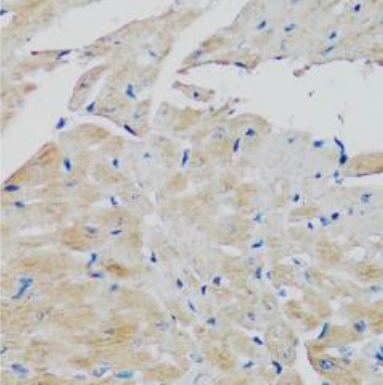

The Medikbio Anti-FGFR2 Antibody (1–100) – Catalog No. MDB23658 is a high-quality rabbit polyclonal antibody developed to detect Fibroblast Growth Factor Receptor 2 (FGFR2), a critical receptor tyrosine kinase involved in cell proliferation, differentiation, angiogenesis, and cancer progression. Designed for optimal performance in Immunohistochemistry (IHC), this antibody provides strong, clear staining with minimal background, enabling precise FGFR2 localization in both human and animal tissues.

Produced using a synthetic peptide corresponding to amino acids 1–100 of human FGFR2, the antibody demonstrates high specificity and robust reactivity with Human, Mouse, and Rat samples—making it ideal for studies involving oncology, developmental biology, and molecular signaling. Affinity purification ensures superior binding performance and reliable IHC detection, even in complex tissue environments.

FGFR2 dysregulation is widely implicated in diseases such as breast cancer, gastric cancer, endometrial cancer, craniosynostosis syndromes, skeletal abnormalities, and developmental disorders. This antibody provides researchers with a powerful tool for mapping FGFR2 expression patterns and investigating receptor-mediated pathways across various biological and pathological models.